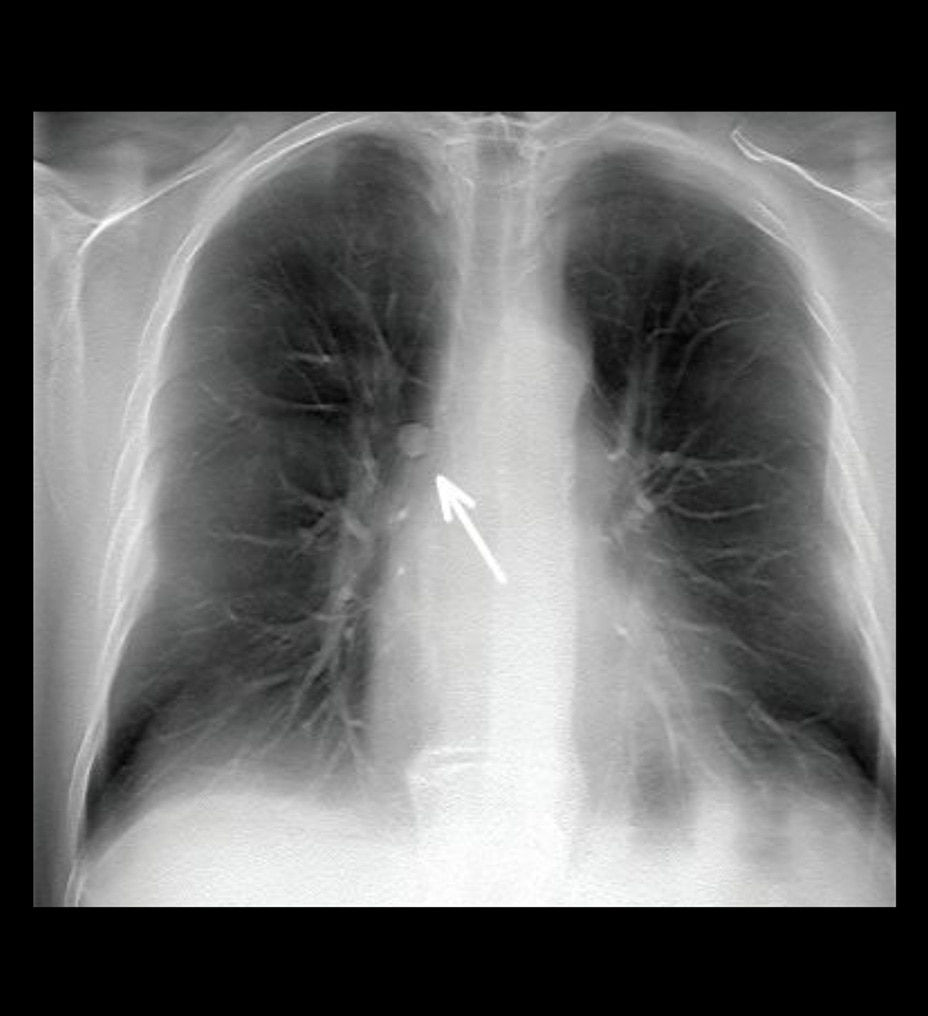

Lung nodule detection

Improve detectability of lung nodules and patient management15

VolumeRAD significantly increases detection sensitivity, enabling radiologists to confidently identify more lung nodules than 2-view chest X-ray. Radiologists also are significantly more accurate at correctly identifying cases requiring follow-up with VolumeRAD than with 2-view chest X-ray.15

• VolumeRAD is 3.6 times more sensitive than chest X-ray in detecting lung nodules 3 mm to 20 mm in diameter, without decreased specificity15

• VolumeRAD is 7.5 times more sensitive than chest X-ray in detecting lung nodules 4 mm to 6mm in diameter, without decreased specificity15